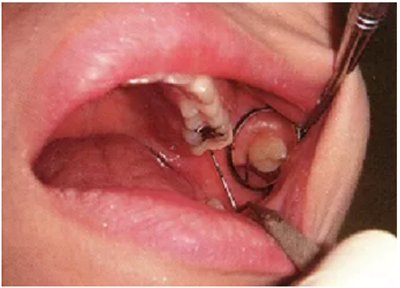

● 鄰接面正下方的探診

鄰接面的正面檢測方法。注意大約是在鄰接面部分的中央位置處,將探針略傾斜插入鄰接面的中央點。

檢測鄰接面正中點下方的牙周袋,探針是無法與牙軸平行插入的。但是緊靠著鄰接點平行于牙軸插入探針,可以檢測到難以檢測的鄰接面牙周袋深。